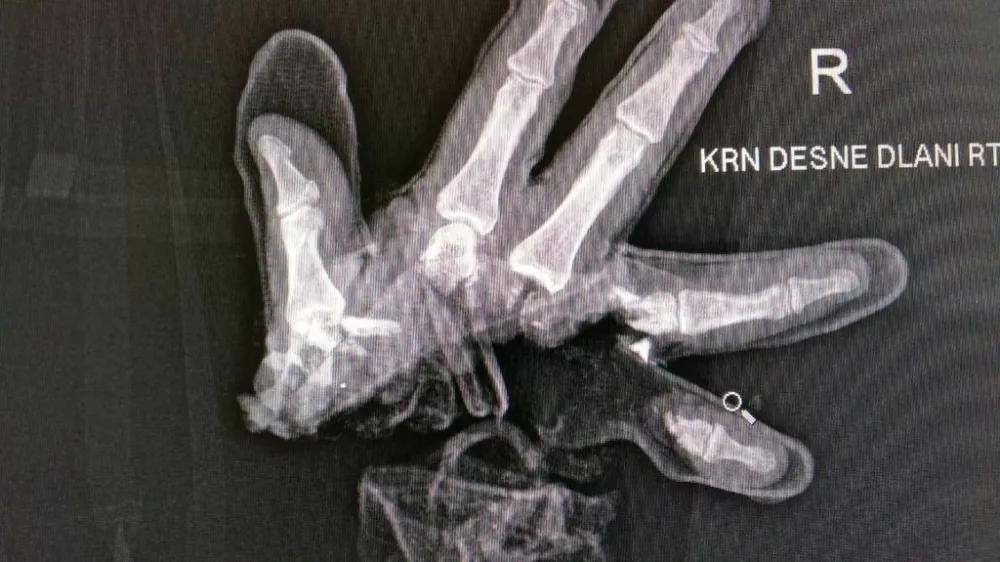

Ljubljanski policisti so sporočili, da se je včeraj ponoči na območju policijske postaje Moste s pirotehniko hudo poškodoval 20-letni moški. Ima hude poškodbe roke, njegovo življenje  po prvih informacijah ni ogroženo.